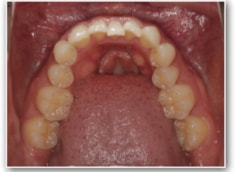

治療開始1年後